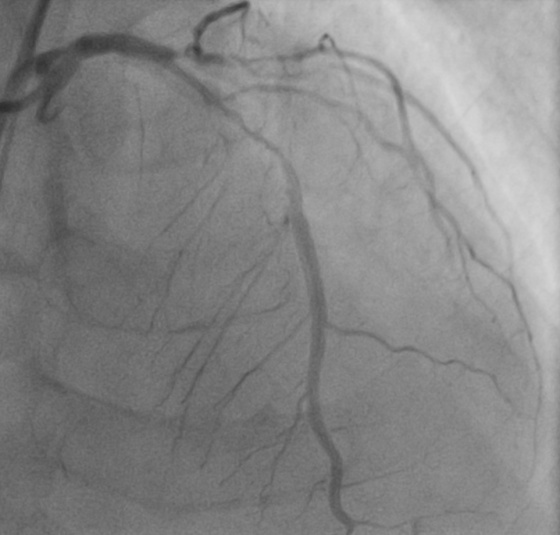

时间就是生命,每一分每一秒都关乎患者安危。抵达医院后,心血管内科在刘学波主任的指挥下迅速响应,医护人员第一时间投入到紧急救治工作中。王明的治疗难度极大,因多年患有糖尿病,心脏三根主要血管均存在重度弥散性钙化病变,外周血管状况也差,且肾功能不全、贫血。经过纠正心衰治疗病情相对稳定后,1月13日,在前期充分的药物治疗基础上,刘学波、来晏、姚义安、钱军等医生对患者行冠脉造影术,提示心脏三根冠脉均存在重度狭窄。其中最重要的左前降支为重度钙化病变,并且术中患者血压偏低,医护人员当机立断,为患者植入主动脉内球囊反搏(iabp),针对严重钙化的血管,来晏主任医师精准运用冠脉内冲击波碎石术(震波球囊)等专业技术破解治疗难题,成功在左前降支植入支架,有效疏通狭窄血管,手术全程顺利,为患者生命安全奠定坚实基础。

支架术前